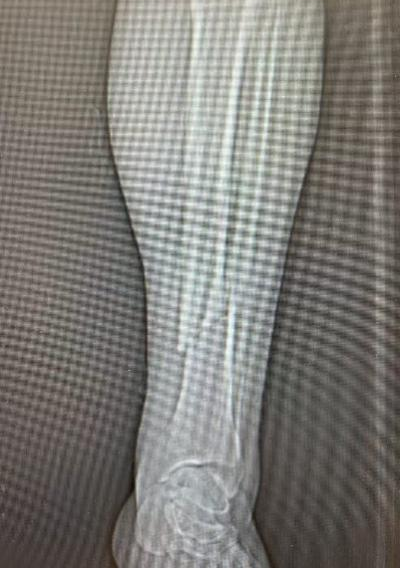

10月4日,59岁张先生不慎被他人电瓶车撞伤致左踝、左小腿疼痛,来院就诊后,王建伟医师团队为患者实行“左胫骨骨折切开复位内固定术”

图片